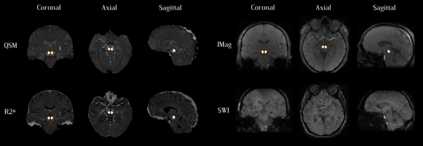

Early and accurate diagnosis of parkinsonian syndromes is critical to provide appropriate care to patients and for inclusion in therapeutic trials. The red nucleus is a structure of the midbrain that plays an important role in these disorders. It can be visualized using iron-sensitive magnetic resonance imaging (MRI) sequences. Different iron-sensitive contrasts can be produced with MRI. Combining such multimodal data has the potential to improve segmentation of the red nucleus. Current multimodal segmentation algorithms are computationally consuming, cannot deal with missing modalities and need annotations for all modalities. In this paper, we propose a new model that integrates prior knowledge from different contrasts for red nucleus segmentation. The method consists of three main stages. First, it disentangles the image into high-level information representing the brain structure, and low-frequency information representing the contrast. The high-frequency information is then fed into a network to learn anatomical features, while the list of multimodal low-frequency information is processed by another module. Finally, feature fusion is performed to complete the segmentation task. The proposed method was used with several iron-sensitive contrasts (iMag, QSM, R2*, SWI). Experiments demonstrate that our proposed model substantially outperforms a baseline UNet model when the training set size is very small.